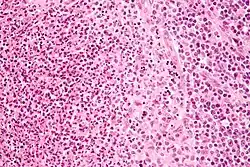

Cat-scratch disease is characterized by granulomatous inflammation on histological examination of the lymph nodes. Under the microscope, the skin lesion demonstrates a circumscribed focus of necrosis, surrounded by histiocytes, often accompanied by multinucleated giant cells, lymphocytes, and eosinophils. The regional lymph nodes demonstrate follicular hyperplasia with central stellate necrosis with neutrophils, surrounded by palisading histiocytes (suppurative granulomas) and sinuses packed with monocytoid B cells, usually without perifollicular and intrafollicular epithelioid cells. This pattern, although typical, is only present in a minority of cases.[16]